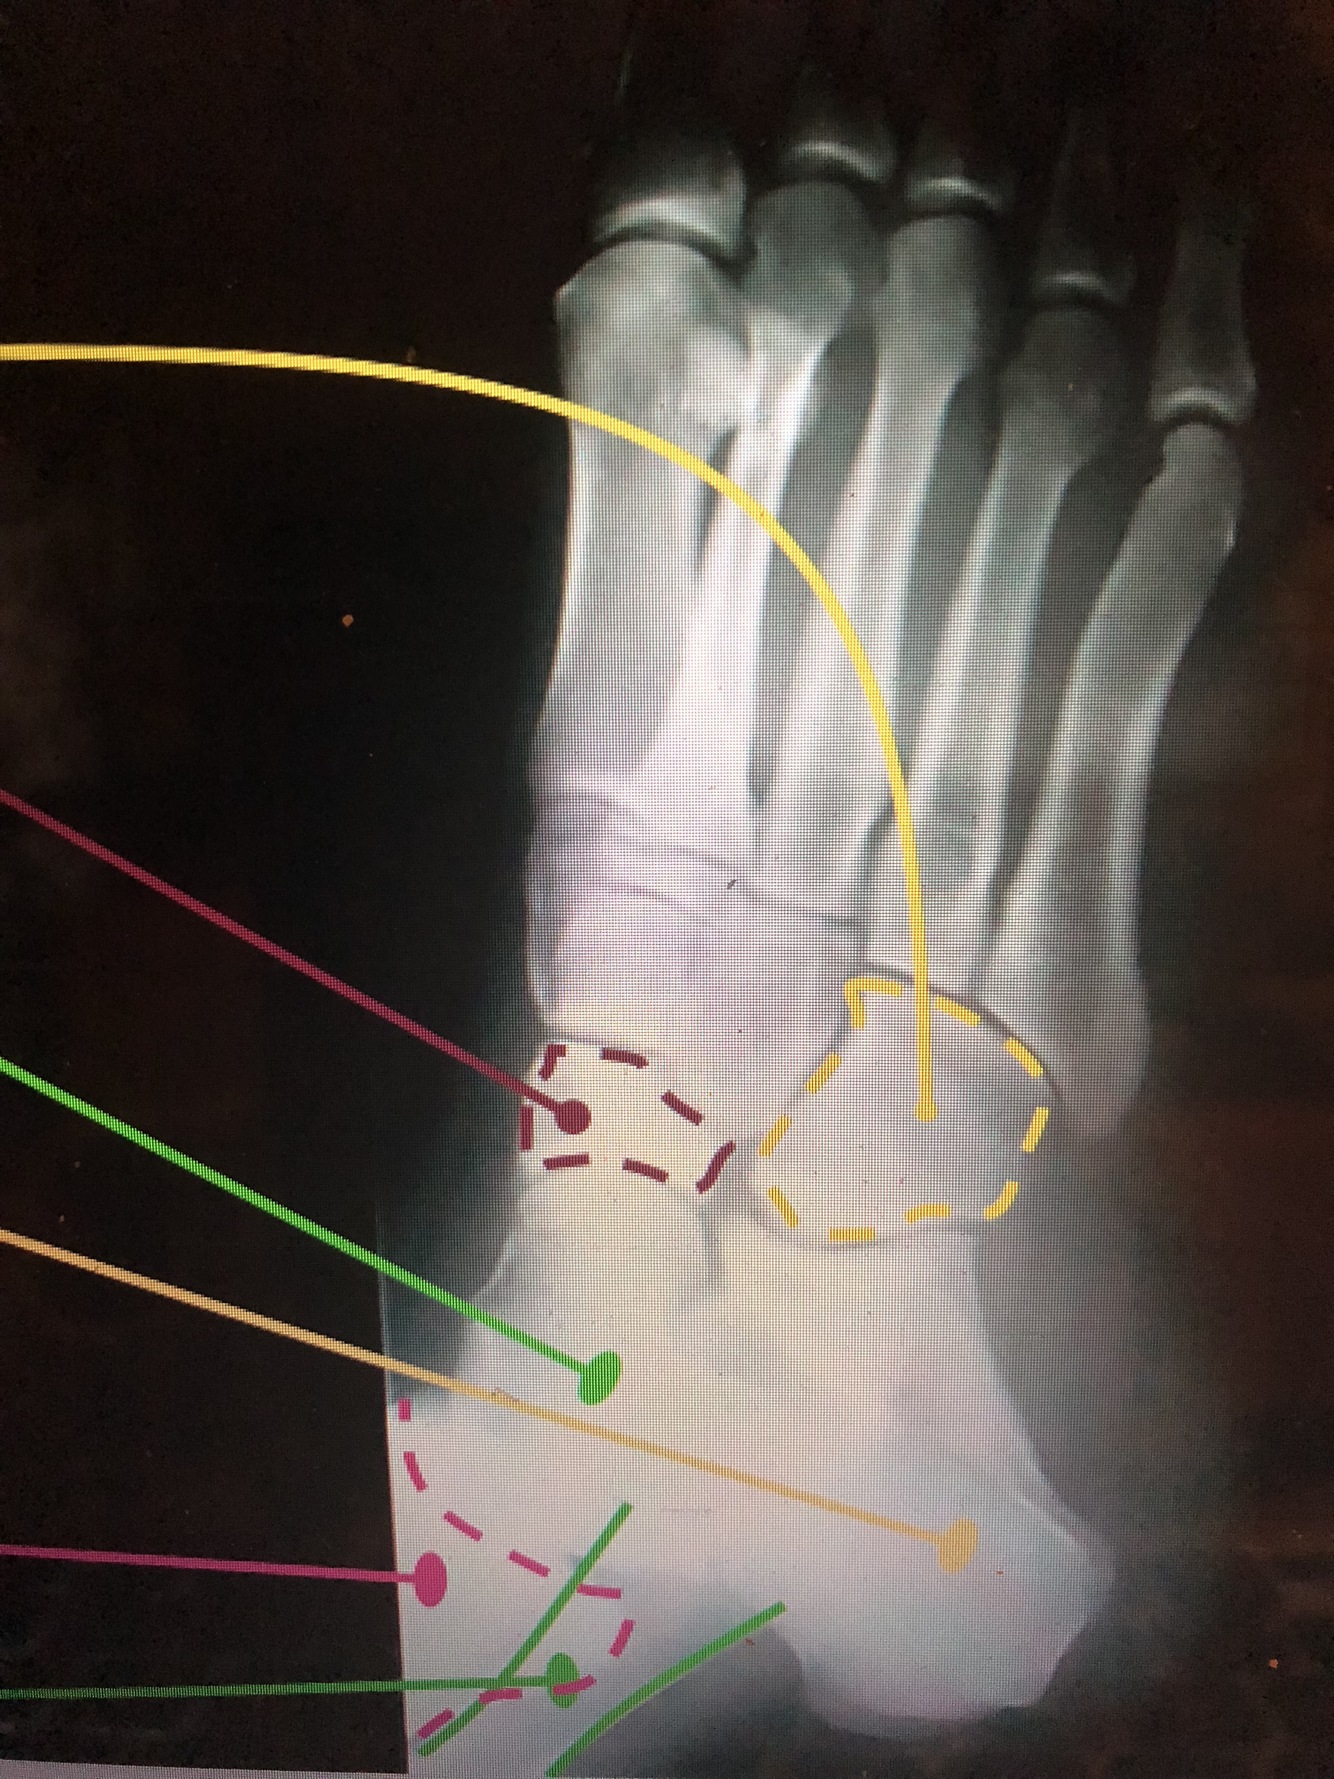

What bone is the dotted yellow line?

Cuboid

What bone is the purple dotted line?

navicular

What bone is the light green?

talus

What bone is the yellow solid dot?

Calcaneus

What bone is pink?

tibia

What bone is the dark green lines?

fibula

What is the dark blue?

Head of the Talus